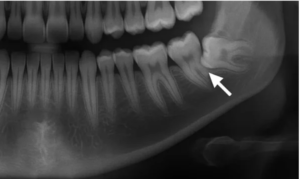

- 親知らず